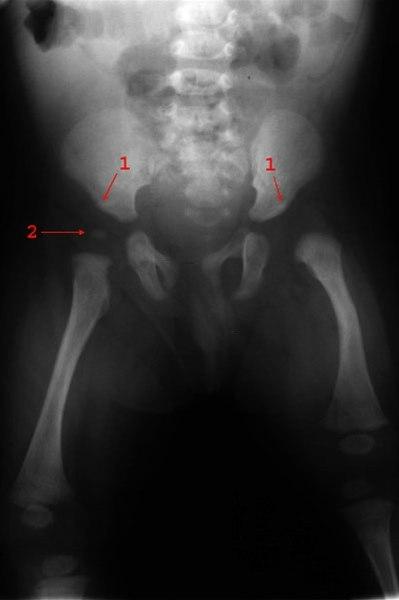

Venstresidig hofteleddsdysplasi med steil acetabulumvinkel, lateralisering av caput femoris og forsinket mineralisering av caputs benkjerne

- Acetabularvinkel

- Benkjerne høyre caput femoris (venstre ikke mineralisert)